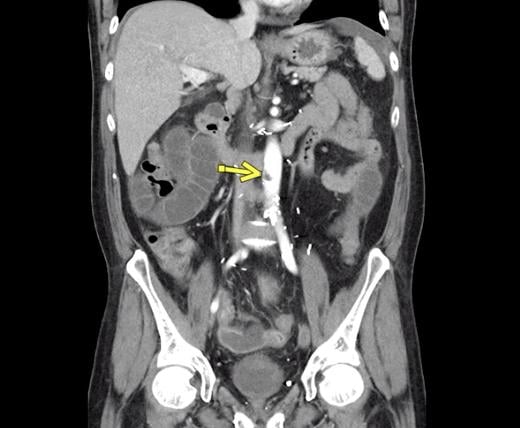

This photo gallery shows the variety of radiological presentations of COVID-19 (SARS-CoV-2) in medical imaging, including computed tomography (CT), radiograph X-rays, ultrasound, echocardiograms and magnetic resonance imaging (MRI). The radiology images show examples of typical COVID pneumonia in the lungs and the numerous complications the virus causes in the body in multiple organs, including the brain, kidneys, heart, abdomen and vascular system.

Ultrasound, especially hand-held ultrasound imaging devices, have become a primary imaging modality for novel coronavirus because of the ease to bag the device and sterilize it after use. CT and mobile X-ray systems are also used as front-line imaging systems for COVID-positive or suspected COVID patients.